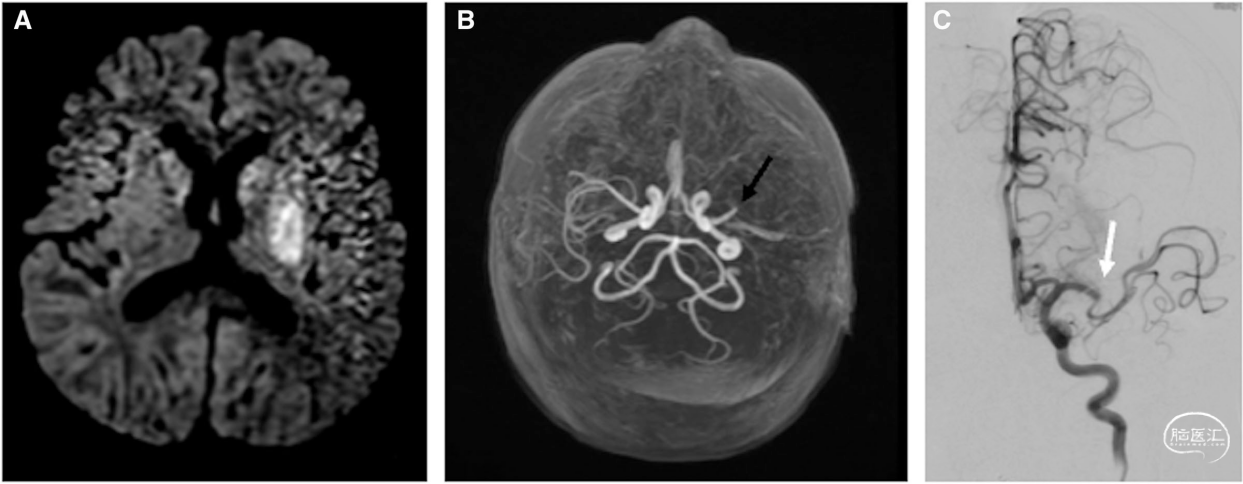

患者男,2岁,有左心发育不良综合征病史,突发肢体僵硬、意识丧失及呼吸暂停,考虑癫痫发作。患者苏醒后右侧肢体无力,并被送至社区医院,而后紧急转至具备儿童卒中救治能力的医疗机构,于发病5小时抵达。到院时,儿童版NIHSS评分为11分(该量表根据儿童发育情况调整,其余评分标准与成人NIHSS一致)。

因患者年龄限制,且已超出4.5小时静脉溶栓时间窗,未予静脉溶栓治疗。急诊头颅MRI/MRA示左侧基底节及小脑梗死,伴M1段远端闭塞(图2A、B),未行灌注成像检查。患者存在心房扑动,超声心动图示心室功能严重减退伴左心室血栓。予心脏电复律后,紧急送入神经介入手术室;脑血管造影示左侧MCA闭塞,远端灌注不佳(图2C)。于发病9小时行取栓术,实现远端再灌注>50%(TICI分级2b级)。考虑此次心源性卒中由先天性心脏病合并心律失常、心室功能不全伴血栓形成引起。

取栓术后,患者转入儿科心脏重症监护室,针对心室血栓启动比伐芦定静脉持续抗凝治疗。卒中后第1天复查头颅MRI/MRA,示左侧基底节缺血灶进展,伴点状出血,M2段远端血栓持续存在。因出现点状出血,暂时停用比伐芦定,但鉴于临床及影像学状态稳定,于第3天重启抗凝,第7天转为口服利伐沙班。予左乙拉西坦预防癫痫发作,疗程7天,期间未再癫痫发作。拔除气管插管后,患者存在混合性失语及右侧偏瘫。经3周住院康复治疗,语言功能恢复并超过发病前基线水平,右侧偏瘫症状极轻微,可快速行走,手部可完成目的性动作。

病例2强调,对于发病24小时内、年龄≥28天的LVO儿童患者,实施取栓治疗具有临床价值,尤其由具备儿童诊疗经验的神经介入医师操作时获益更显著(2026年AIS指南2b类推荐)。灌注成像可辅助成人取栓决策,但儿童尚缺乏界定缺血风险组织的相关参数。此外,儿童侧支循环代偿能力更强,也会影响灌注成像结果。成人灌注成像中采用的改良阿尔伯塔卒中项目早期CT评分(ASPECTS)系统,以及基于容积和时间界定梗死核心与缺血半暗带的标准,可能并不适用于儿童。同时,该病例突显了先天性心脏病可增加儿童卒中风险。加强对高危儿童群体的家长、患儿及医护人员的卒中症状宣教,对提升卒中早期识别率至关重要。